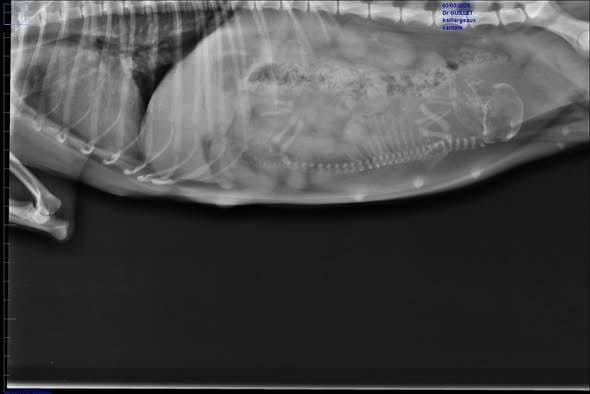

La seconde radio est celle de Cantate, toute petite naine limite toy, et elle a bien un chiot, mais unique et déjà très gros à 58 jours. Pour une fois, je vais suivre sa courbe de température et certainement césarienne en vue. Je fais très rarement des radios, mais là, j’avais un doute sur un gros chiot ou deux. Deux ça passerait certainement, mais vu la taille du chiot, là, c’est moins sur.